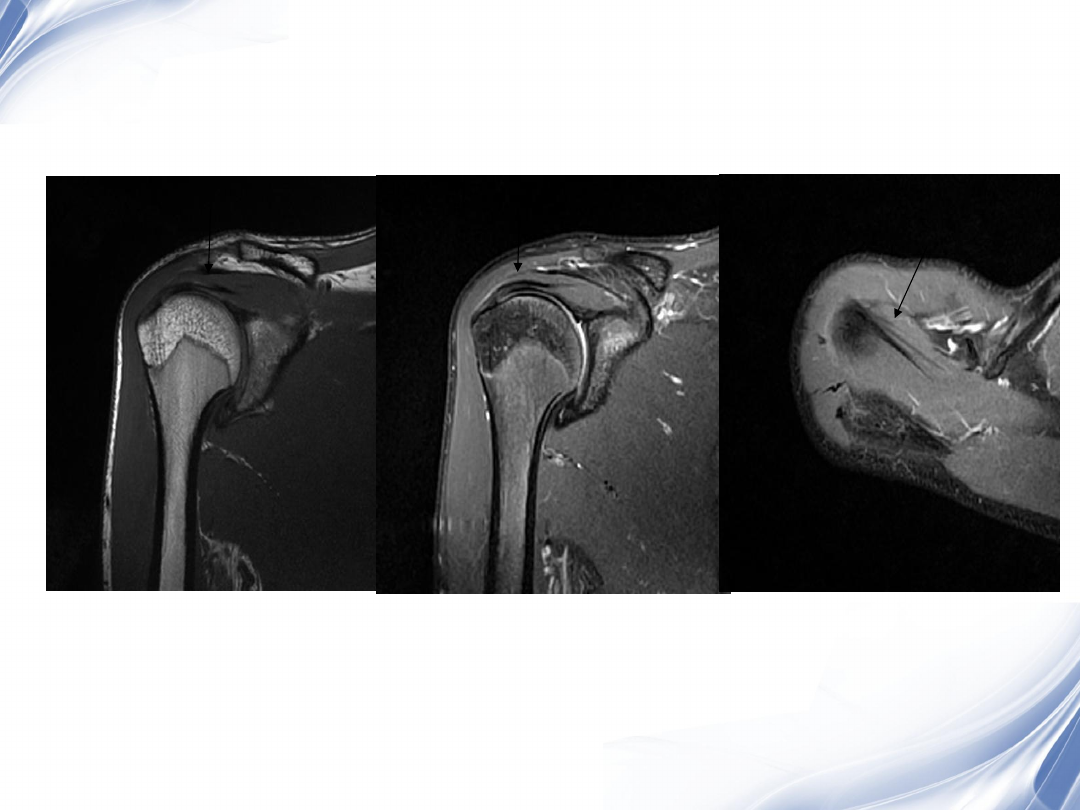

斜冠状位(临床最常用)

T2

T1

31

斜矢状位

冈上肌出口,肩袖诊断不如

斜冠状位

冈上肌及肌腹脂肪浸润成度

,评估手术与否

32

34

肩袖全层撕裂

正常MRI